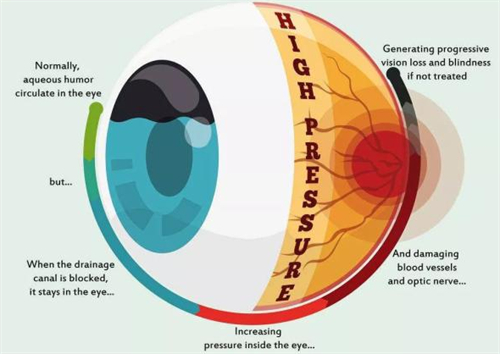

北京青光眼手术领域正经历“比较准化、小创口化、个性化”的技术升级。

朝聚眼科的小创口技术、民众眼科的全术式覆盖、普祥眼科的疑难病例攻坚、希玛林顺潮眼科的国内外术式本土化、茗视光眼科的比较准检查体系,共同构建起多层次诊疗网络。

患者可根据自身病情重度程度、手术耐受性、术后改善需求等因素,选择比较适合的医疗机构。

随着3D打印、人工智能等技术的融入,青光眼手术的比较准度与可靠性将持续提升,为患者带来更多光明希望。